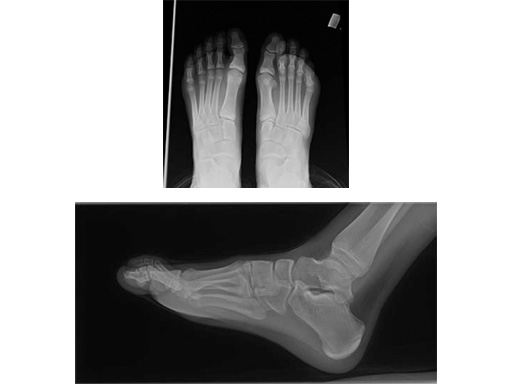

16-year-old male

Proximal first metatarsal growth-plate injury resulting in haluxvalgus. Arthrosis of first tarsometatarsal and second metatarsal hammer toe. Pain during activities and in general shoe wear.

Case provided by Carl Hasselman, Pennsylvania, USA

First MTP fusion and modified McBride with a distal soft-tissue release and second metatarsophalangeal (MTP) capsulotomy. A mini tight rope was used to hold and reduce the alignment of the first metatarsal. The X-plate was used to hold rigid fixation of the fusion. A K-wire was used for the second MTP capsulotomy.